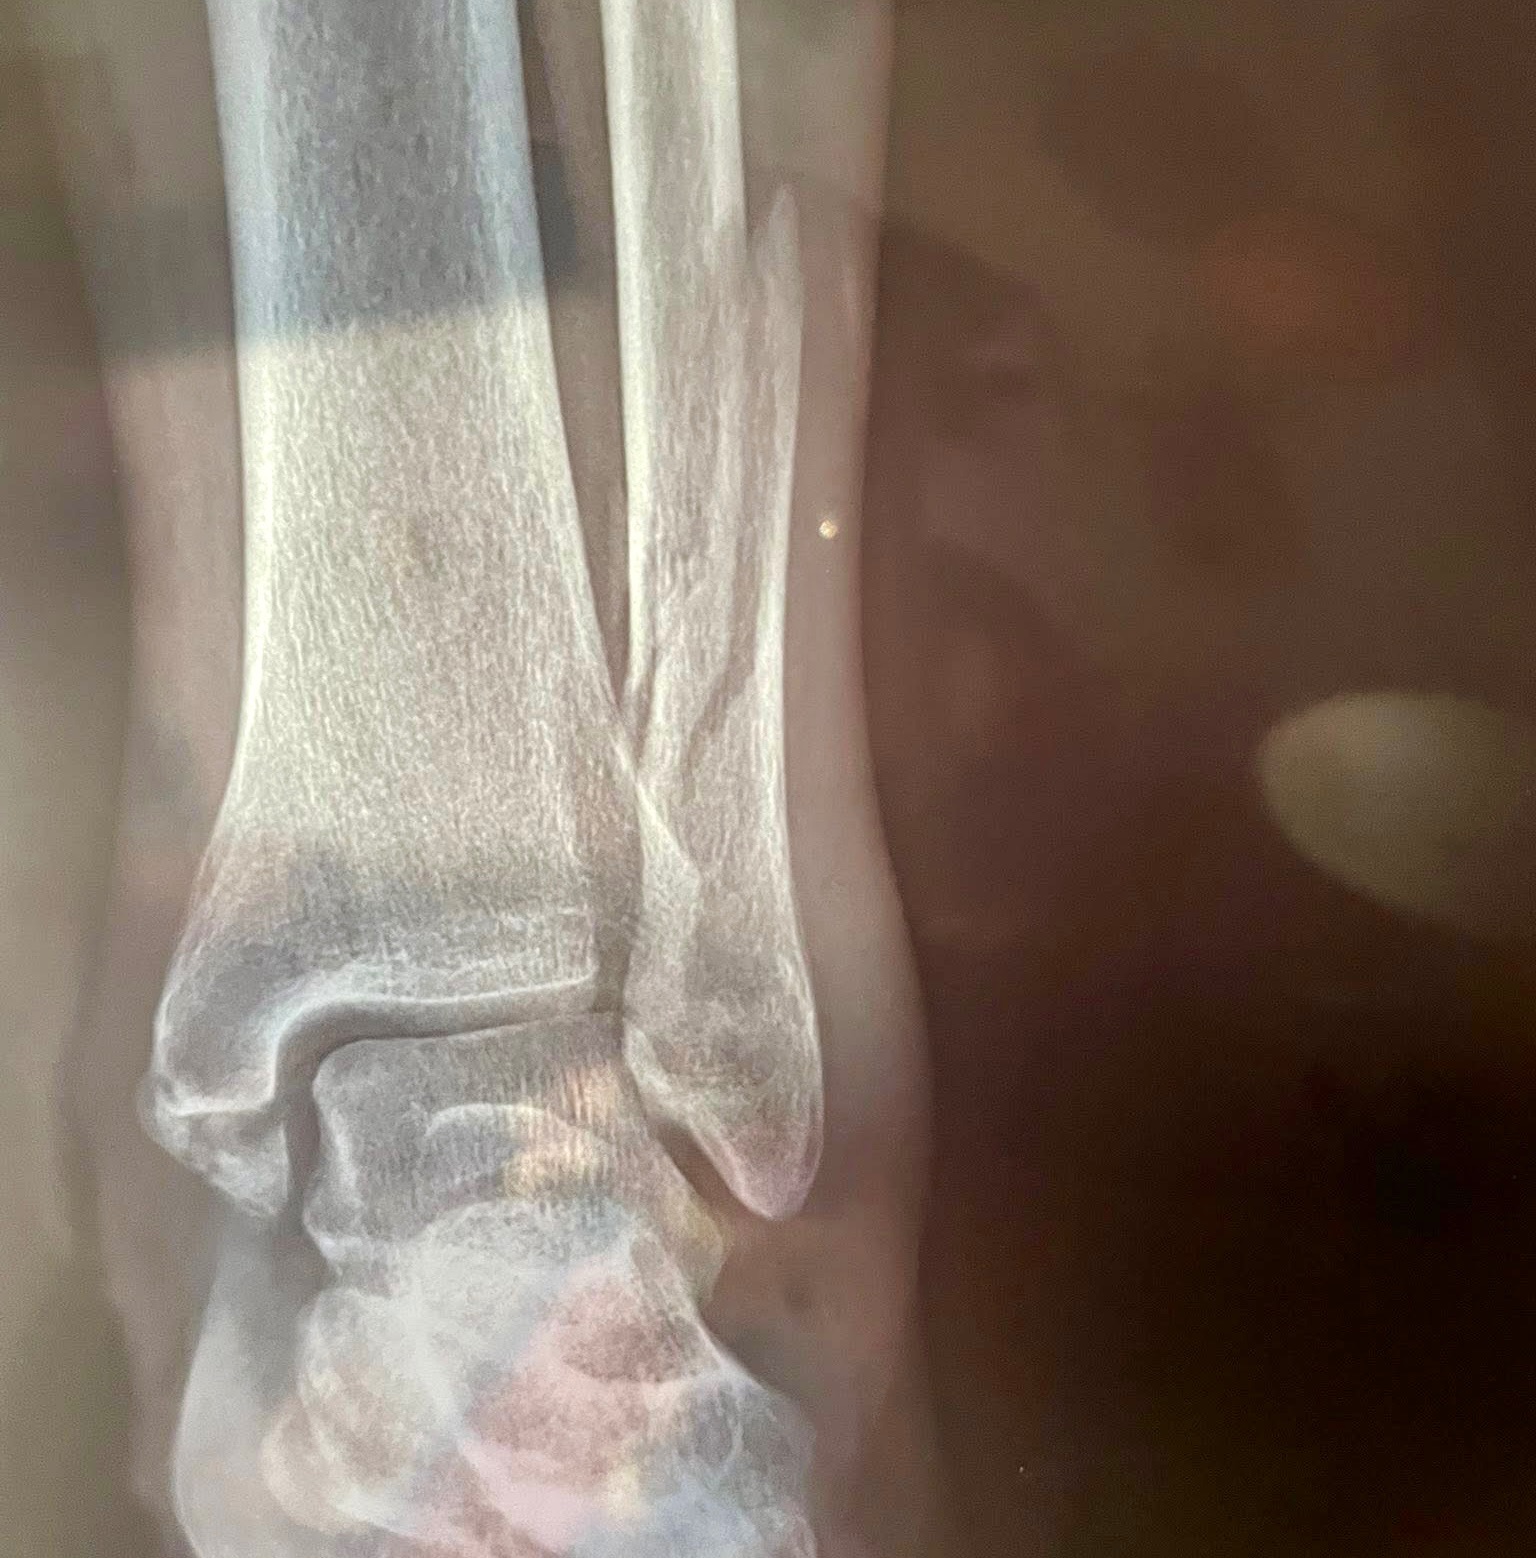

Two days ago, Marki suffered a serious fall and broke her leg. She was finally seen at the hospital today, where doctors confirmed she needs surgery with two plates placed in her leg so she can walk again.

She’s in Hospital Medassist in Emiliano Zapata, Puerto Vallarta, waiting for the swelling to reduce so doctors can perform this surgery.

The estimated cost for this surgery is 170,000 pesos ($9,560 USD), and her insurance is not covering the procedure. The surgery is needed as soon as possible.